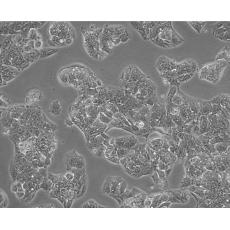

Hep G2

中文名稱 人肝癌細胞

生長特性 adherent

形態特征 epithelial

細胞描述 該細胞來源于一名15歲的白人少年的肝癌組織。該細胞表達甲胎蛋白、白蛋白、α-2-巨球蛋白、α-1-抗胰蛋白酶、轉鐵蛋白、α-1-抗凝乳蛋白酶、結合珠蛋白、銅藍蛋白、纖溶酶原、補體C4、C3激活物、纖維蛋白原、α-1酸性糖蛋白、α-2-HS-糖蛋白、β-脂蛋白、視黃醇結合蛋白;表達胰島素受體和胰島素樣生長因子IGFⅡ的受體;該細胞具有3-羥基-3-甲酰輔酶A還原酶和肝甘油三酯脂肪酶的活性。目前尚未證明該細胞中有HBV基因組。